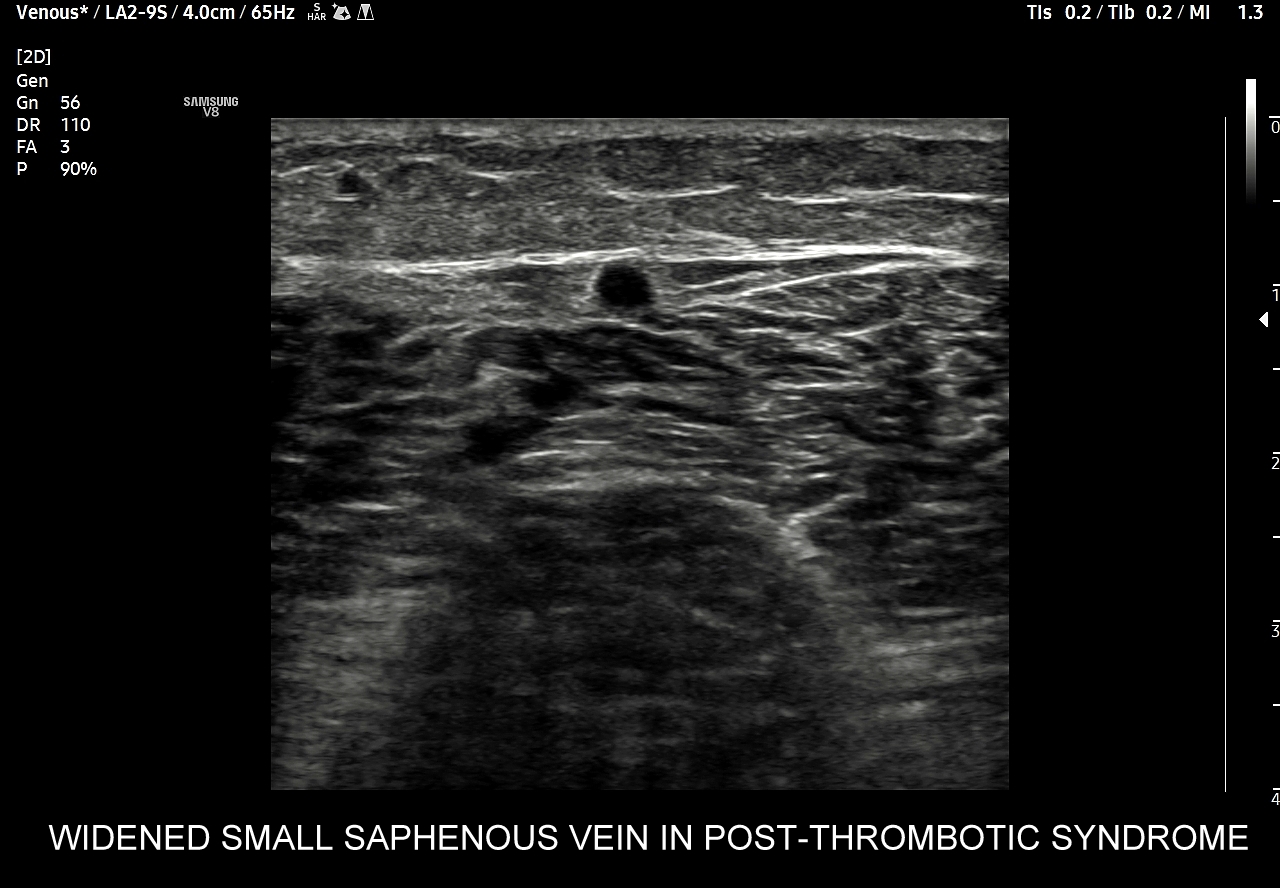

42. Patologie żył kończyn dolnych, w tym niewydolność żył powierzchownych i głębokich, żylaki, zakrzepica żył powierzchownych, zakrzepica żył głębokich, zespół pozakrzepowy.

Dzień żylny w ramach Kursu dedykowany jest dopplerowskiemu badaniu żył, w szczególności w obrębie kończyn dolnych. Otóż to właśnie w tym obszarze ujawniają się najczęściej choroby układu żylnego takie jak zakrzepica żył głębokich, zakrzepica żył powierzchownych, niewydolność żył powierzchownych i żylaki podudzi, niewydolność żył głębokich i zespół pozakrzepowy, które to badający lekarz powinien umieć rozpoznać. W trakcie interdyscyplinarnego Kurs USG Doppler Cedum ® omawiane są również hemodynamika krążenia żylnego w fizjologii i w stanach patologicznych; cele diagnostyczne, w tym planowanie zabiegów angiochirurgicznych i endowaskularnych w obrębie żył; a także nauczane są techniki funkcjonalnego badania żył kończyn dolnych i żył miednicy. Kurs obejmuje także tematykę dotycząca żyły głównej dolnej i jej brzusznych dopływów, żył szyjnych oraz żył kończyn górnych.